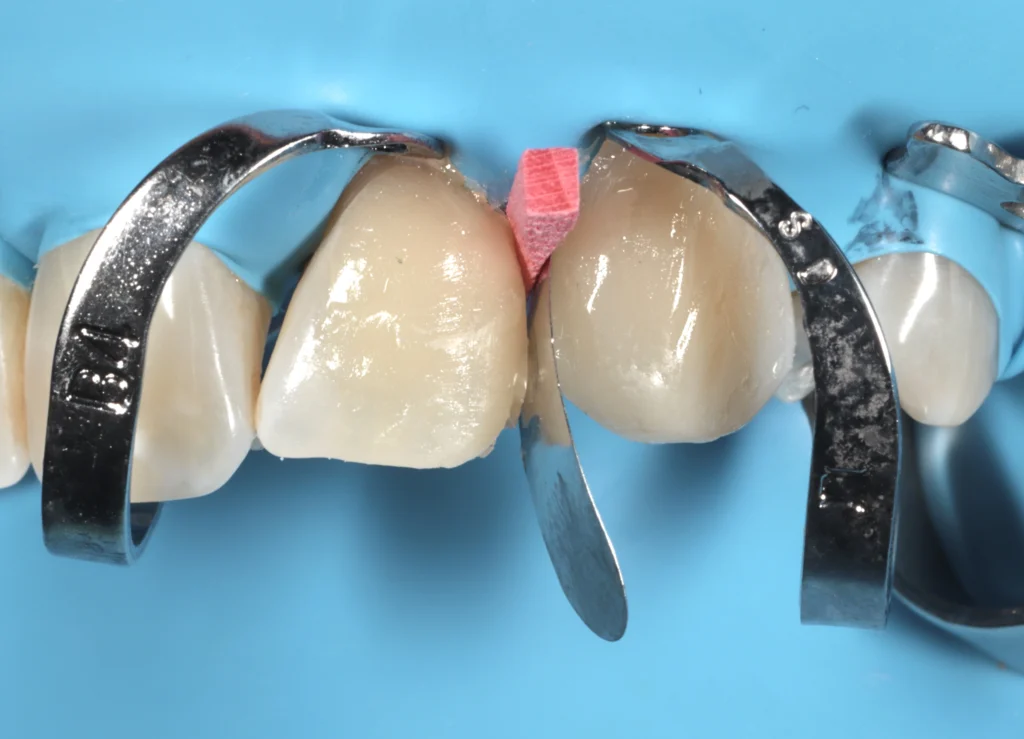

White Spots Treatment in Beirut

Restore a uniform, natural tooth color without damaging your enamel.

White spot treatment (ICON infiltration) is a modern, minimally invasive solution to eliminate white stains caused by braces or enamel defects. This painless procedure blends the color of your teeth without drilling, helping you achieve a more aesthetic and balanced smile in just one session.